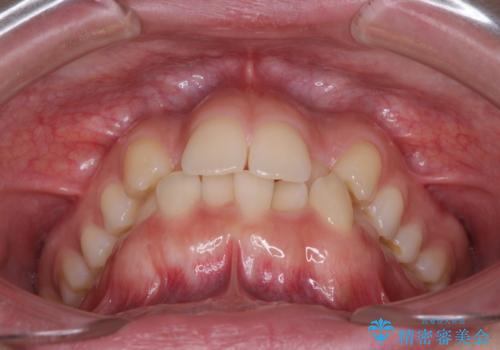

叢生の程度は中等度であったため、IPR(歯と歯の間を削る)と歯列の側方拡大をメインに、インビザラインを用いて歯列を改善することとしました。

また、下顎骨の右側変位による右側臼歯の咬合を改善させるよう試みることとしました。

右側の咬合改善を目標に様々な手法を用いましたが、骨格的なズレによる不正咬合はインビザラインでは改善することができませんでした。